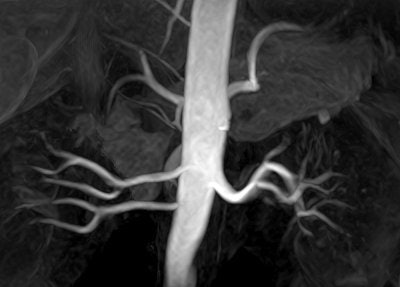

![]() |

| Above, contrast-enhanced renal MRA on a Magnetom Avanto scanner. Imaging protocol included 3D FLASH with TR/TE 2.5/1/1 msec in 20 seconds. Below, 3D TrueFISP fat-saturated navigator-gated noncontrast renal MRA. Time: Five minutes. TR/TE 900/1.6 msec. Inversion time 600 msec (work-in-progress). Images courtesy of Siemens Medical Solutions USA. |